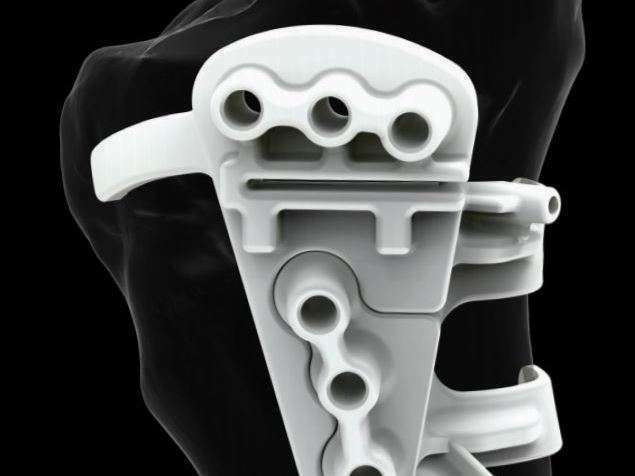

Cette intervention consiste à réaxer le membre inférieur. Elle débute par deux coupes osseuses (ostéotomie) au niveau du tibia proximal et/ou au niveau du fémur distal. Ensuite deux gestes peuvent être réalisés : une ouverture du trait d’ostéotomie avec l’ajout d’une cal pour maintenir la correction, ou une fermeture du trait d’ostéotomie. Une fois la correction obtenue, les deux fragments osseux sont solidement maintenus par une plaque vissée.

Le matériel pourra être retiré une fois que l’ostéotomie est consolidée et que le processus de remodelage osseux est terminé (environ 1 à 2 ans post-opératoire). Ce qui permettra un gain fonctionnel et une diminution de la gêne causée par la plaque.